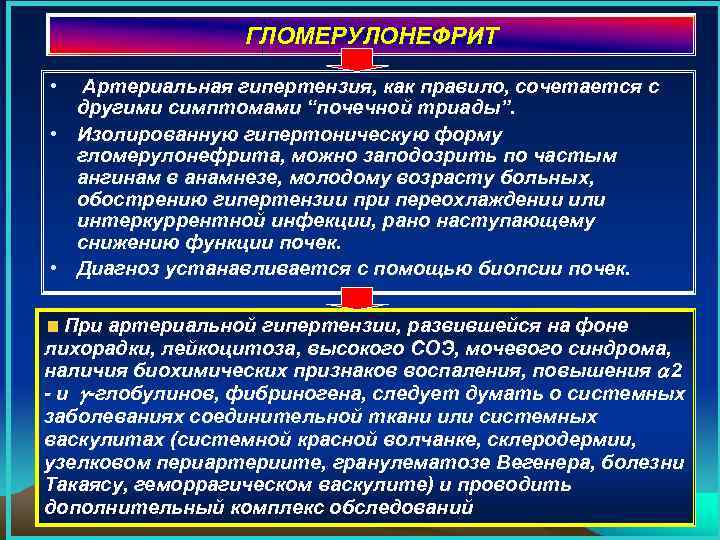

ГЛОМЕРУЛОНЕФРИТ • Артериальная гипертензия, как правило, сочетается с другими симптомами “почечной триады”. • Изолированную гипертоническую форму гломерулонефрита, можно заподозрить по частым ангинам в анамнезе, молодому возрасту больных, обострению гипертензии при переохлаждении или интеркуррентной инфекции, рано наступающему снижению функции почек. • Диагноз устанавливается с помощью биопсии почек. При артериальной гипертензии, развившейся на фоне лихорадки, лейкоцитоза, высокого СОЭ, мочевого синдрома, наличия биохимических признаков воспаления, повышения 2 - и -глобулинов, фибриногена, следует думать о системных заболеваниях соединительной ткани или системных васкулитах (системной красной волчанке, склеродермии, узелковом периартериите, гранулематозе Вегенера, болезни Такаясу, геморрагическом васкулите) и проводить дополнительный комплекс обследований

ГЛОМЕРУЛОНЕФРИТ • Артериальная гипертензия, как правило, сочетается с другими симптомами “почечной триады”. • Изолированную гипертоническую форму гломерулонефрита, можно заподозрить по частым ангинам в анамнезе, молодому возрасту больных, обострению гипертензии при переохлаждении или интеркуррентной инфекции, рано наступающему снижению функции почек. • Диагноз устанавливается с помощью биопсии почек. При артериальной гипертензии, развившейся на фоне лихорадки, лейкоцитоза, высокого СОЭ, мочевого синдрома, наличия биохимических признаков воспаления, повышения 2 - и -глобулинов, фибриногена, следует думать о системных заболеваниях соединительной ткани или системных васкулитах (системной красной волчанке, склеродермии, узелковом периартериите, гранулематозе Вегенера, болезни Такаясу, геморрагическом васкулите) и проводить дополнительный комплекс обследований